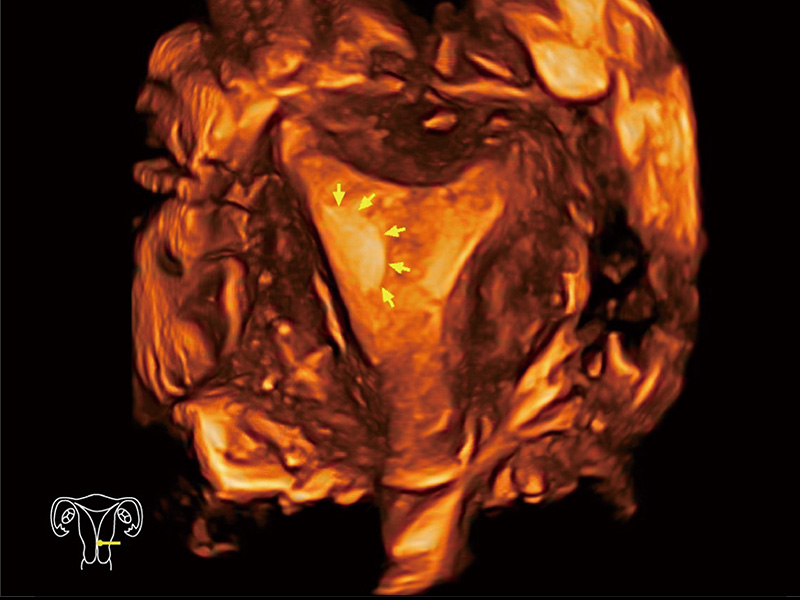

腔内容积探头

腔内三维成像技术获得显著提升,超大扇角在满足日常基础扫查的同时,支持卵泡自动测量及多种三维渲染模式,为您提供更多的诊断信息,尤其是在子宫畸形的诊断,内膜及肿瘤占位观测中起到了重要的作用。

临床图

中央型宫腔粘连

单角子宫